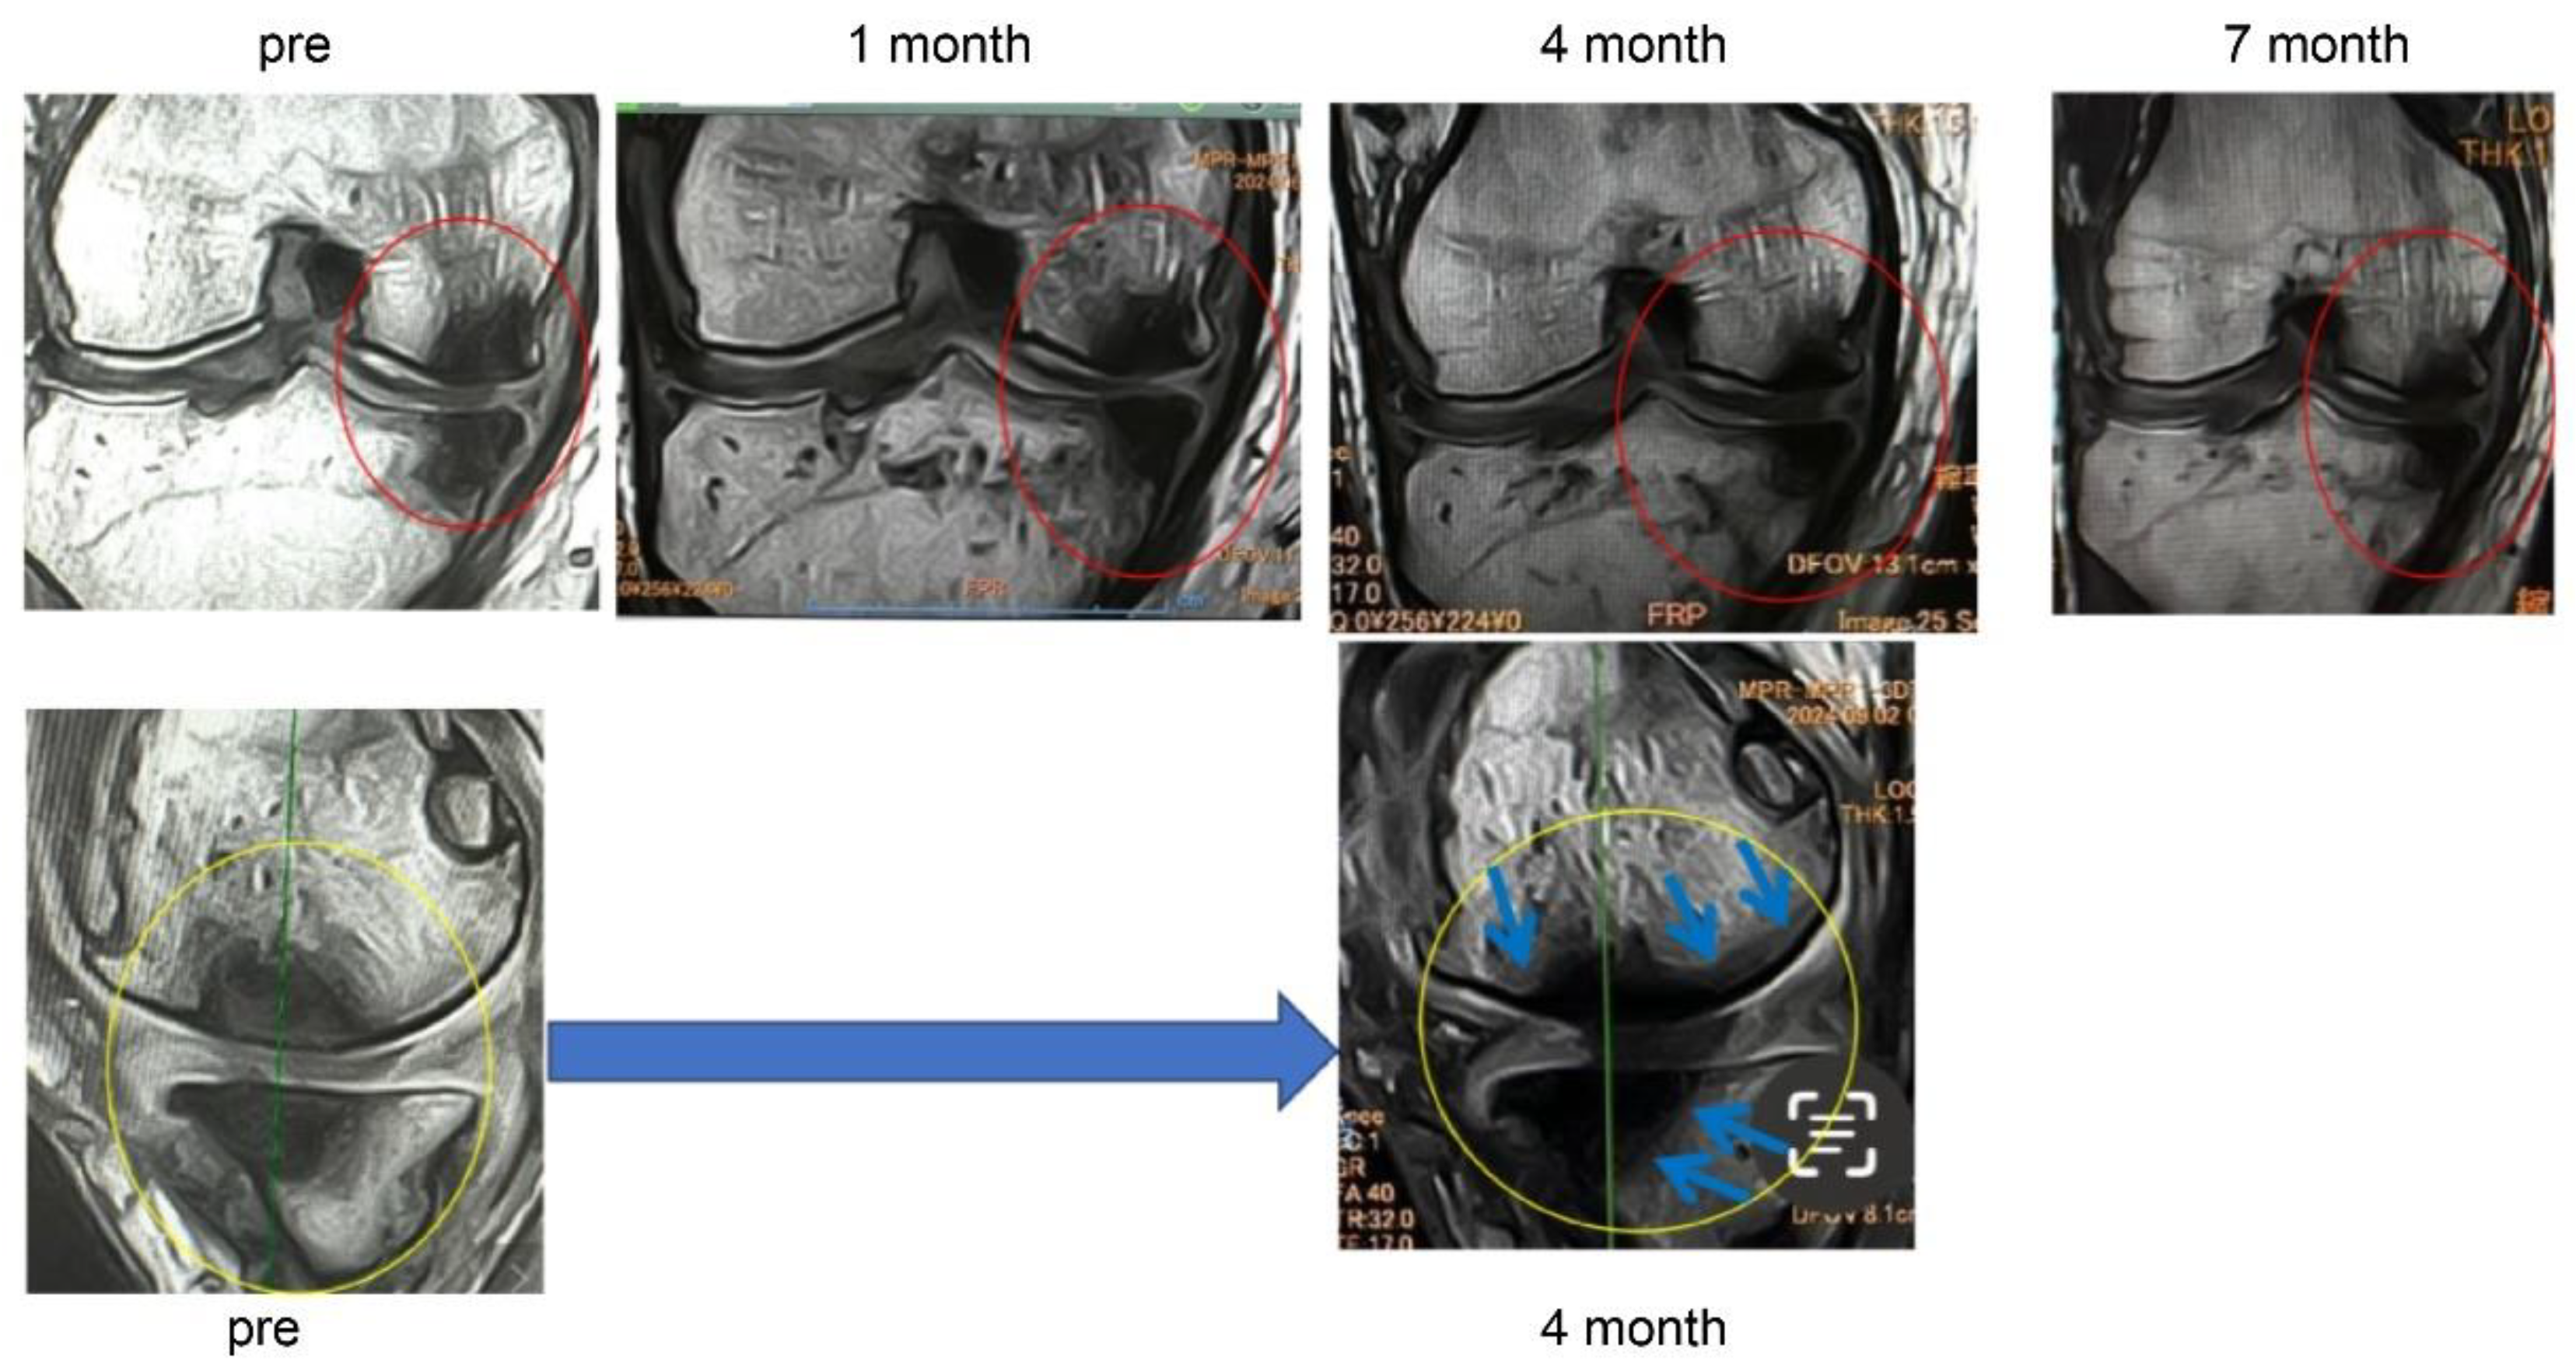

In Case 3 (

Figure 8), a 70-year-old male, at baseline, MRI revealed the disappearance of the cartilage layer and subchondral bone plate tear associated with a BML in the medial femoral condyle and tibial plateau. At 1-month post-treatment, mosaic-like high-signal areas extended throughout the region surrounding the BML. At 4 months, the mosaic-like areas and a reduction in BML were observed. At 7 months, although no improvement in the cartilage layer was detected, areas of bone sclerosis had expanded to cover the joint surface, indicating progression of bone repair. It was considered that the repair process was still in progress.

Figure 8.

Temporal MRI changes after treatment. At baseline, a BML with cartilage layer loss and SBP tear was observed in the medial femoral condyle and tibial plateau. At 1 month, mosaic-like high-signal areas spread around the BML. At 4 months, BML reduction and mosaic-like changes were seen. At 7 months, no cartilage recovery was evident, but bone sclerosis expanded to cover the joint surface.